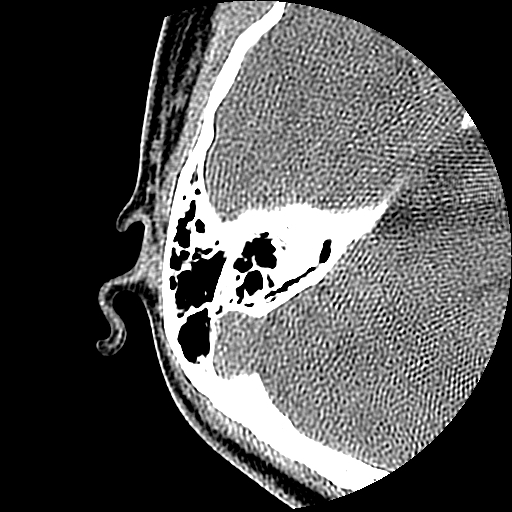

以下是引用随光逐影在2009-8-19 7:25:00的发言:[br]右侧慢性中耳乳突炎,右侧中耳腔及外耳道肉芽肿或胆脂瘤形成。